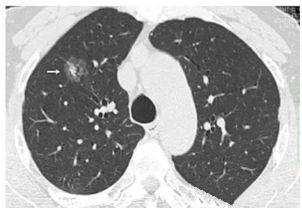

肺部小結(jié)節(jié)通常是指影像檢查(X線或者CT)中發(fā)現(xiàn)的直徑≤2cm的類圓形病灶,≤3cm的稱為結(jié)節(jié),>3cm的稱為腫塊。

也有學(xué)者認(rèn)為,分得太細(xì)并無意義,例如2.2cm的結(jié)節(jié)與1.9cm的小結(jié)節(jié),臨床上并沒有本質(zhì)的區(qū)別。在這里我們統(tǒng)一把≤3cm的結(jié)節(jié)統(tǒng)稱為肺部小結(jié)節(jié),在肺部小結(jié)節(jié)中,60%—70%為良性結(jié)節(jié),30%—40%的結(jié)節(jié)方為惡性結(jié)節(jié),所以,發(fā)現(xiàn)肺部小結(jié)節(jié)切勿驚慌。

結(jié)節(jié)的大、小與良、惡性有一定的相關(guān)性,當(dāng)肺部結(jié)節(jié)>3cm的病灶多為惡性,而微小的結(jié)節(jié),良性的可能性居多。

我們常看到的影像學(xué)描述中的“磨玻璃結(jié)節(jié)(GGO)”,其中一部分是非典型腺瘤樣增生(AAH)或原位腺癌(AIS),結(jié)節(jié)內(nèi)部的實(shí)變與生長速度的加快(范圍變大)常意味病變性質(zhì)的轉(zhuǎn)變,可以逐步演變?yōu)槲⒔櫹侔∕IS)、浸潤性腺癌(IAC)。